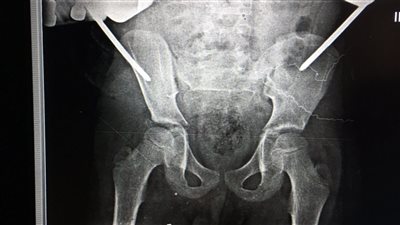

تثبيت كسر خلعى بمفصل الحوض

وقام الفريق الطبي بقسم جراحة العظام بمستشفي الزقازيق العام، بقيادة الدكتور محمد راشد رئيس القسم، والدكتور أحمد عبدالسلام استشاري جراحة العظام، والدكتور أحمد نوفل مقيم جراحة العظام، تحت إشراف الدكتور جلال بليغ مدير المستشفى، بإجراء جراحة متقدمة ذات طابع خاص، لتثبيت كسر خلعي بمفصل الحوض باستخدام مثبت خارجي، لطفل يبلغ من العمر 9 سنوات، وذلك بعد إجراء كافة الفحوصات الطبية والأشعات اللازمة، والمريض الآن بحالة جيدة ومستقره، ويتلقي العلاج اللازم بقسم جراحة العظام تحت متابعة الأطباء بالمستشفى